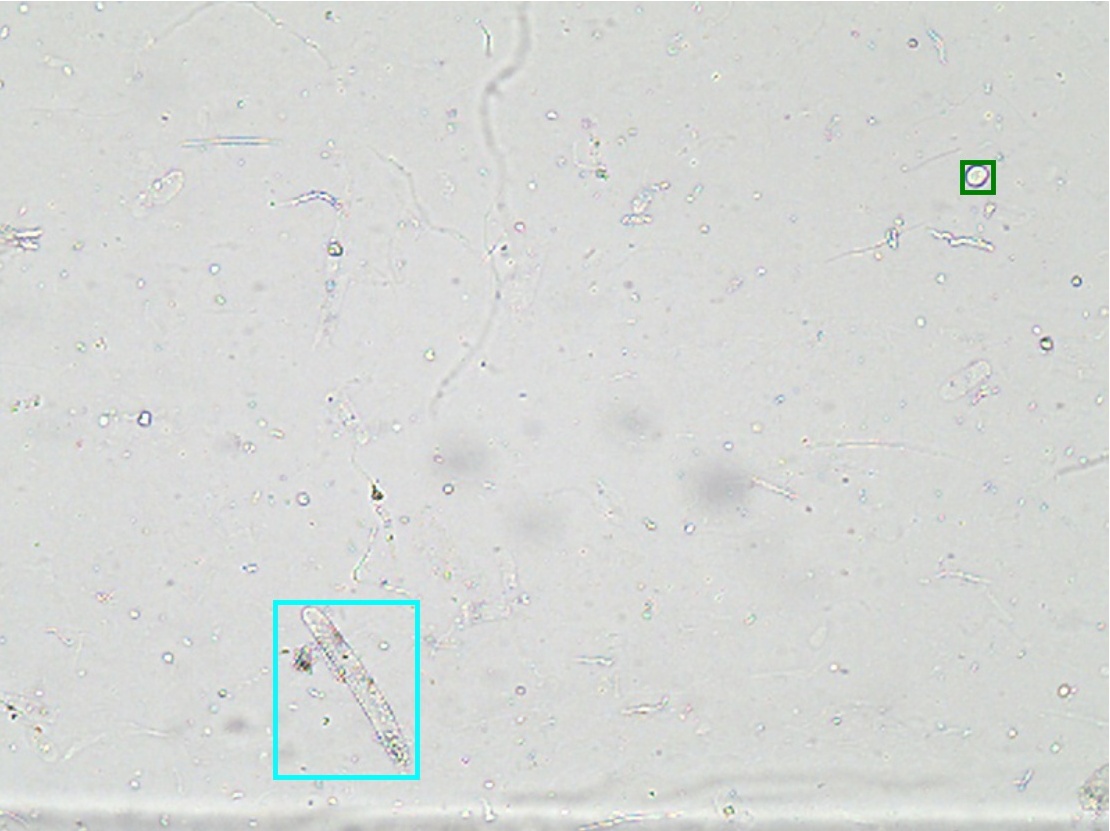

In order to perform our study, we first establish the urinalysis micro-images database that is marked with ground truth boxes by clinical experts. All 6,804 annotated color images have a size of 800 x 600, which include 8 categories of urinary sediment particles, i.e., erythrocyte (eryth), leukocyte (leuko), epithelial cell (epith), crystal (cryst), cast, mycete, epithelial nuclei (epithn) and noise. Specifically, eryth, leuko, crystal, mycete and epithn are only annotated at high-power field, epith and cast only at low-power field. Figure 5 shows 7 categories of urinary sediment particles from our database, each of which includes many subcategories with various shapes.

Figure 4: Selected samples of urinary sediment particle.

\Romannum7 : detection results of cast

Figure 8: Selected detection examples of urine particles on urinalysis test set. We show detections with scores higher than 0.7. All examples are divided into 7 groups, where 5 groups are at high-power field (i.e., erythrocyte, leukocyte, crystal, mycete, epithelial nuclei ) and the other 2 groups at low-power field (i.e., epithelial cell, cast ). In each group: (a) shows original image with ground truth boxes; (b-d) are Faster R-CNN detections separately on ZF, VGG-16 and ResNet-50 networks with a anchor scales of {322,642,1282,2562,5122}superscript322superscript642superscript1282superscript2562superscript5122\{32^{2},~{}64^{2},~{}128^{2},~{}256^{2},~{}512^{2}\}; (e) shows detection results on PVANet; (f) shows detection results on SSD300 model. For the ground truths and detection boxes, different categories use only different colors: eryth (red), leuko (black), epith (green), crystal (magenta), cast (cyan), mycete (yellow). As shown in this figure, the performance of SSD is inferior to Faster R-CNN, and it misses a lot of small objects.